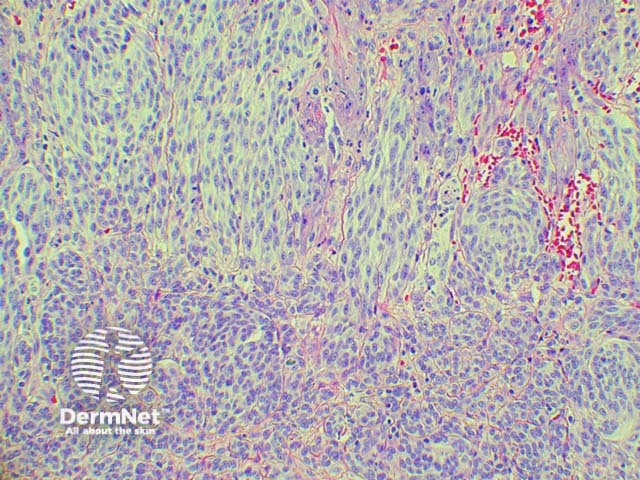

Figure 2